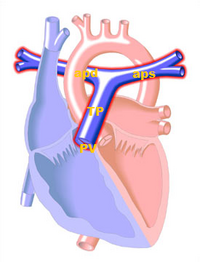

Anatomy

The pulmonary artery carries deoxygenated blood from the right ventricle to the lungs. It is the only artery that carries deoxygenated blood transported.

The pulmonary trunk (TP) starts from the pulmonary valve is ± 5 cm and ± 2 cm in diameter. Then splits into two branches, the trunk, the left-hand (aps) -, and right pulmonary artery (APD), which carry the oxygen-depleted blood to the corresponding lungs.